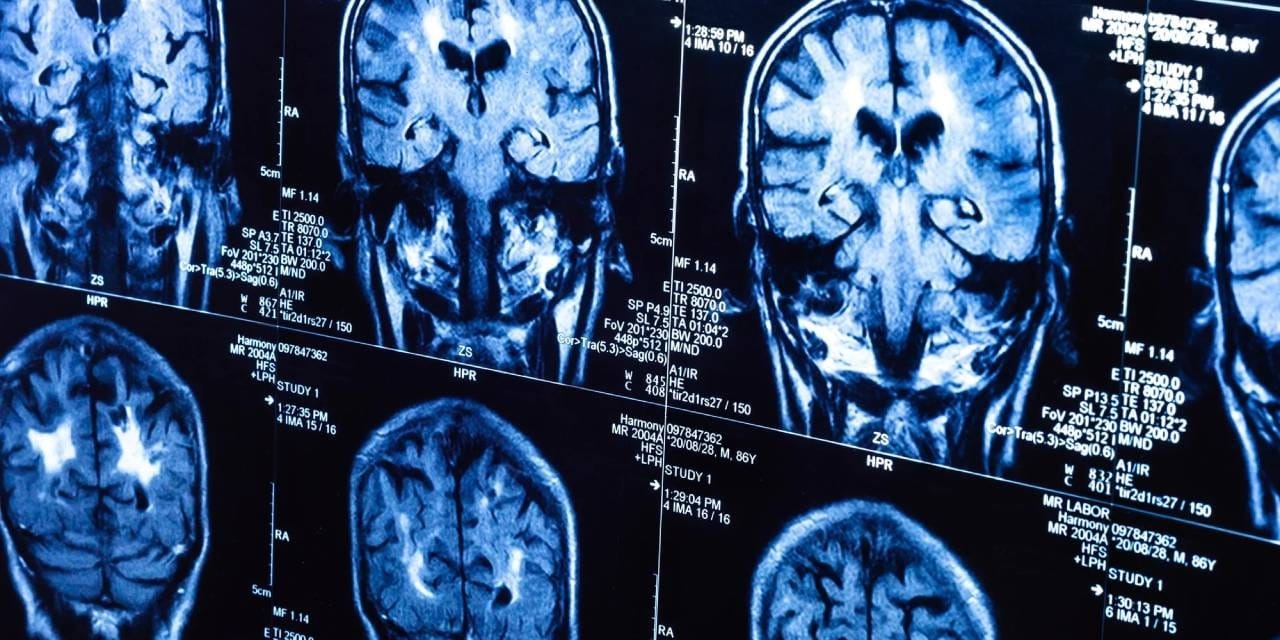

Bilim insanları, UK Biobank’ta yer alan 15 binden fazla yetişkinin verileriyle sağlıklı beyin yaşlanmasını tanıyan bir yapay zeka modeli geliştirdi. Model, pandemiden önce tarananlarla pandemi sırasında taranan iki grubun beyin yaşlarını karşılaştırdı.

Buna göre, pandemi sürecinde insan beyninin yaşlanma hızı ortalama 5,5 ay öne çekildi.